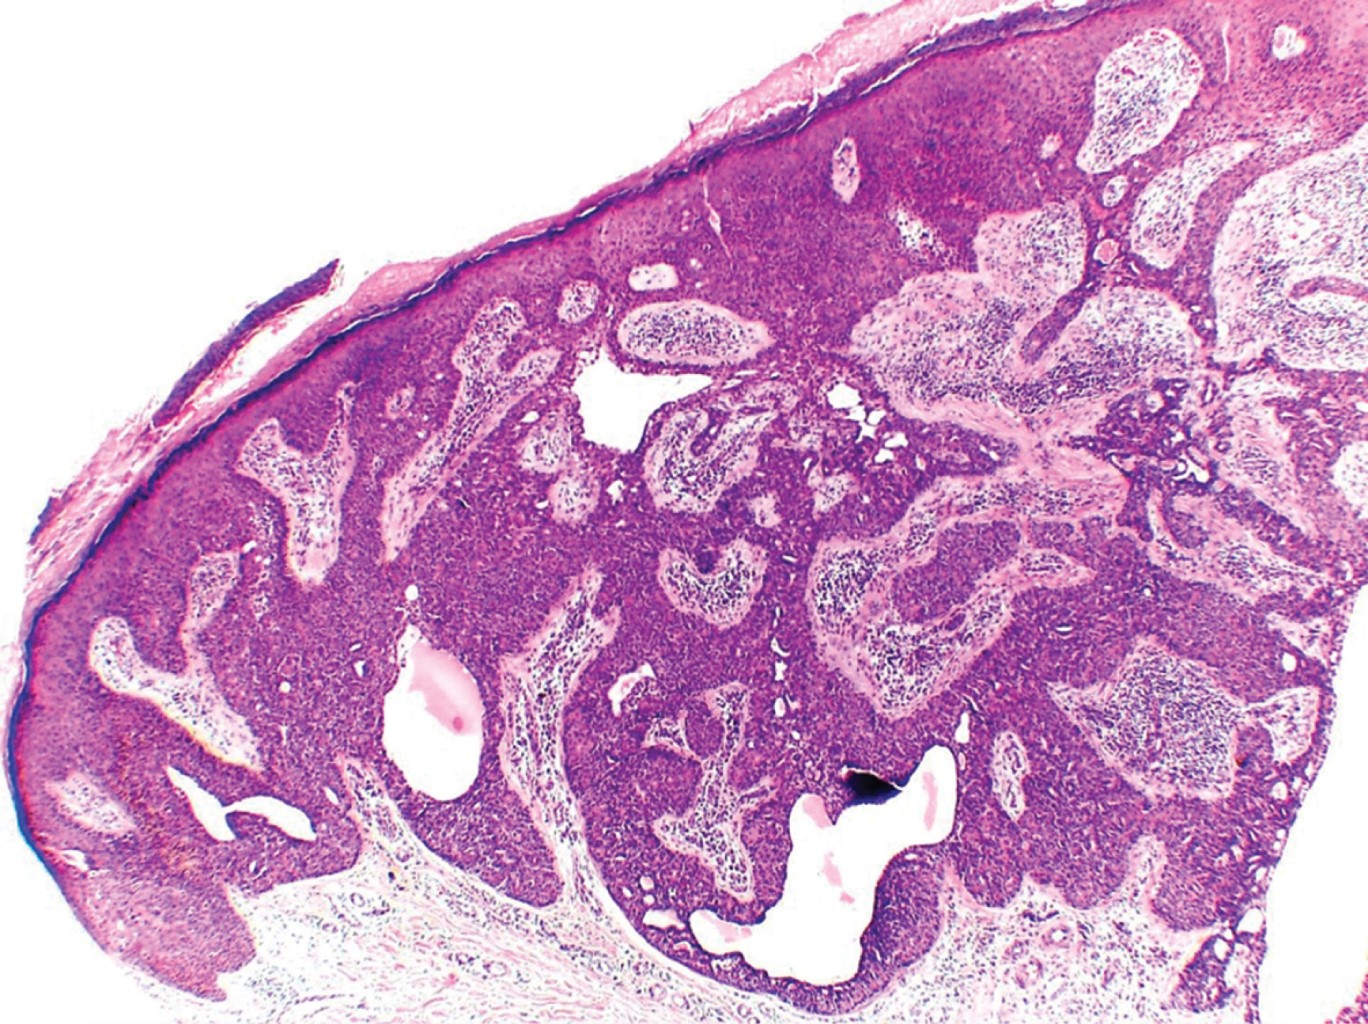

Con la sospecha clínica de probable poroma ecrino se realiza biopsia excisional. El estudio histopatológico reporta neoformación Exofítica, cuya epidermis muestra hiperqueratosis paraqueratósica (Figura 3). En todo el espesor de la dermis se observan cordones tumorales conectados con la epidermis, los cuales se anastomosan atrapando papilas (Figura 4); están constituidos por células de núcleos basofílicos, algunas de las cuales presentan núcleos grandes e hipercromáticos, mitosis anormales y metaplasia escamosa; presentan estructuras ductales y pigmento melánico, rodeados por una moderada reacción inflamatoria (Figuras 5 y 6). El diagnóstico histopatológico fue de porocarcinoma ecrino. En el Servicio de Dermatooncología de esta Unidad se efectúa extirpación quirúrgica más amplia, con margen de 7 cm, con reparación del defecto llevando a cabo un injerto, sin evidenciar lesión tumoral remanente en la histopatología. Al considerarse un tumor con alto potencial metastásico, se envía al paciente a hospital de tercer nivel para hacer estudios de extensión y seguimiento.

Figura 3

Figura 4